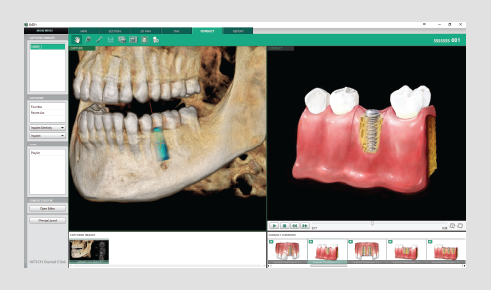

• 3 click implant simulation

• Collision detection

• Bone density

• Oblique view mode

FEATURING VATECH’S VIRTUAL CONSULTATION TOOL

With over 200 unique animations, VCT gives you the tools to not

only educate patients on treatment plans, but also show how

this plan is relevant to their specific case.

• Adjustable automatic implant collision detection function between multiple implants and/or nerve canal